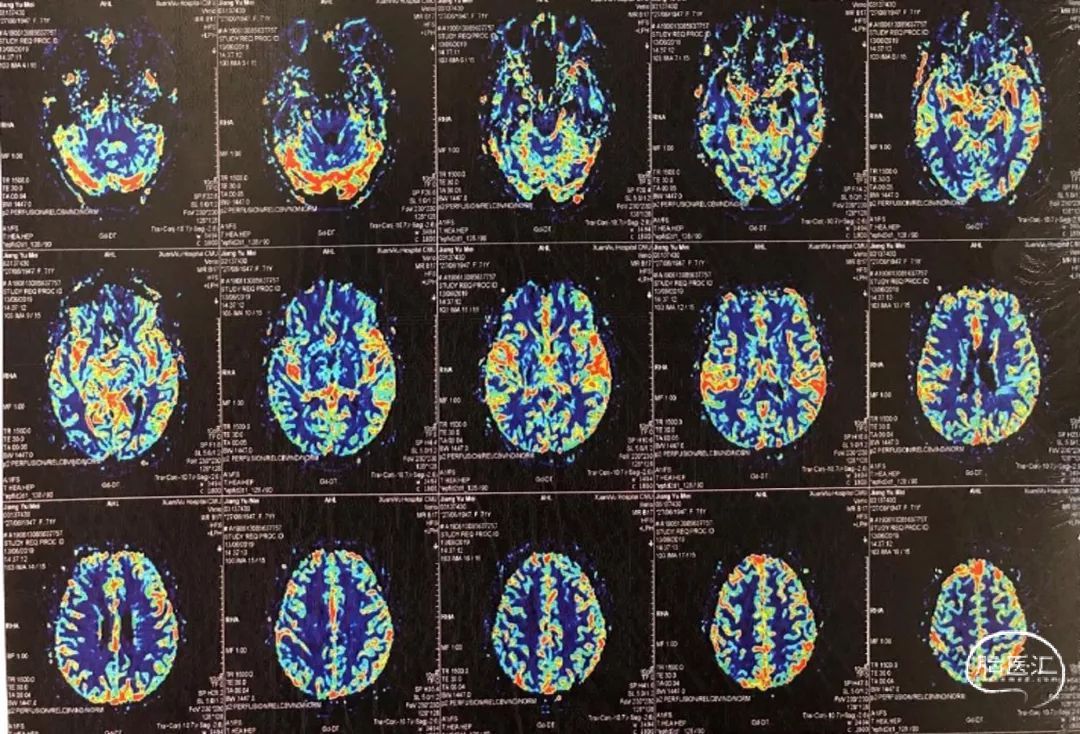

没有颅内出血,急诊复查造影,左侧颈动脉支架内通畅,左侧前循环颅内动脉显影良好,再次除外急性脑梗死,给与静脉乌拉地尔控制血压、甘露醇脱水降颅压治疗后,患者病情稍有缓解,NIHSS 12分,同时查灌注成像(图5)、TCCD(图6)未提示术后高灌注表现。

图5:DSA下行脑灌注检查(到达时间、达峰时间)双侧无明显差异

患者转至监护室继续控制血压、脱水降颅压治疗,病情逐步好转。次日复查头颅核磁(图7),脑肿胀明显减轻,但DWI也提示在左侧半球散在点状高信号,核磁灌注成像(图8),双侧半球基本对称。TCD(图9)提示左侧半球血流速度正常。

图8:核磁灌注成像,双侧无差异